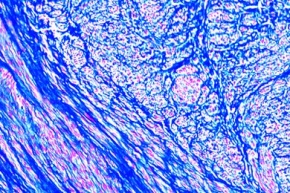

Mikropräparat - Gebärmuttermyom, Myoma uteri

12,14 €

inkl. 19 % USt zzgl. Versandkosten

Zum Artikel